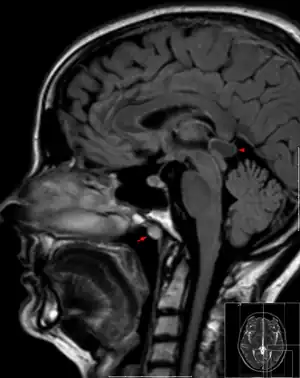

| Tornwaldt cyst imaged on sagittal MRI (FLAIR). The cyst appears hyperintense in the midline of the nasopharynx (arrow). In this case there is also a cyst of the pinealis gland (arrowhead) showing a signal intensity slightly higher than the CSF. | |